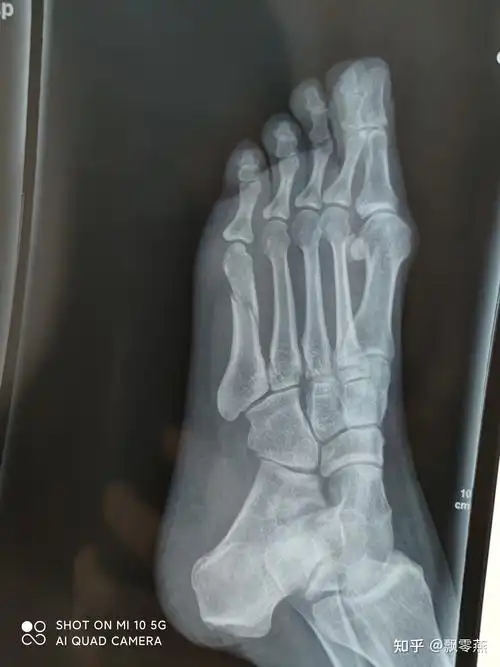

左脚第五趾骨基底骨折恢复过程记录

脚第5跖骨骨折35

12岁初一,右脚趾骨骨折,已经打了12天石膏,25天复诊时能不能拆了,这样

患者教育:足趾骨折(基础篇)_骨折_介绍_症状表现_检查_治疗方式_日常